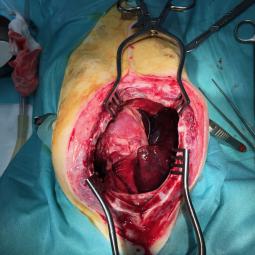

Les chirurgies thoraciques:

Ces interventions sont plus delicates que les chirurgies abdominales, une assistance respiratoire est obligatoire. Les principales interventions sont: les lobectomies pulmonaires, les pericardectomies, la ligature du canal arteriel persistant, l'exerese de masses mediastinales ...